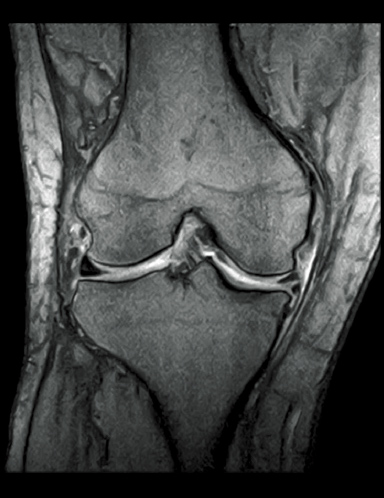

FatSat-PDWI

T2WI

T2*WI RadialStack